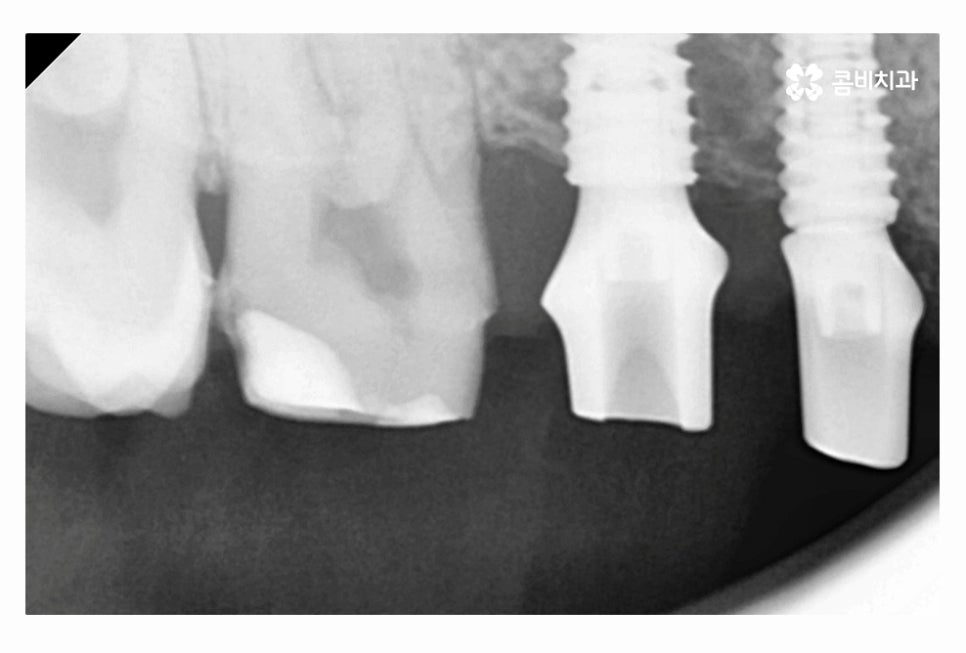

임플란트의 원리는 잇몸에 임플란트를 식립하고 골유착 과정을 통해서

단단하게 인공치근이 고정이 되고 보철물을 연결하여

자연치아의 기능 거의 대부분을 회복할 수 있는데요.

20대임플란트 치료를 하시는 분들의 경우 충치, 사고 등으로

치아를 잃게 되는 경우가 많기 때문에 치료는 크게 어려운 경우는 많지 않지만

당뇨나 전신질환 등이 있거나 잇몸 상태가 좋지 않은 경우에는

20대라고 하더라도 보다 섬세한 치료가 중요하다고 할 수 있어요.